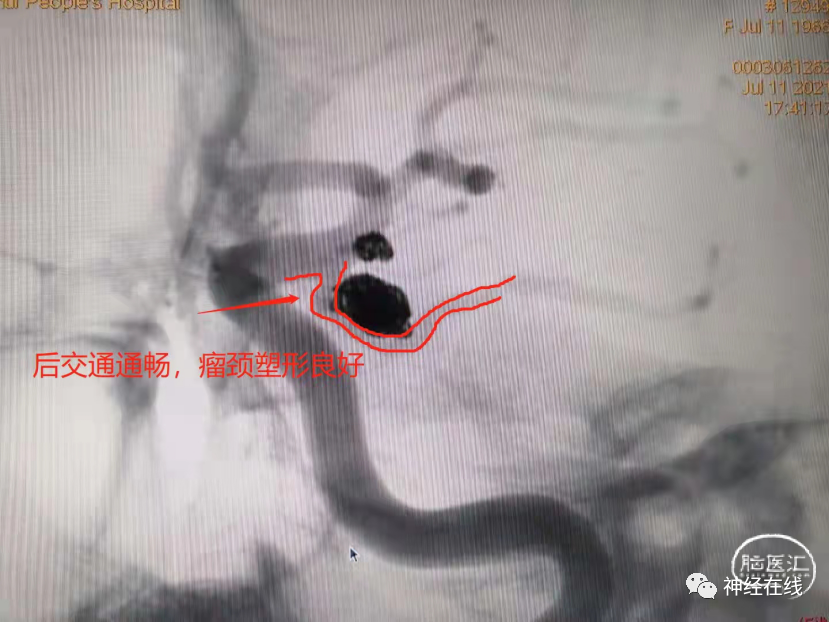

长条状破裂后交通动脉瘤弹簧圈栓塞病例